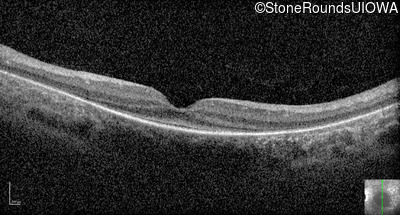

Optical Coherence Tomography - Right - Light Perception

Exemplar

Optical Coherence Tomography - Left - Light Perception